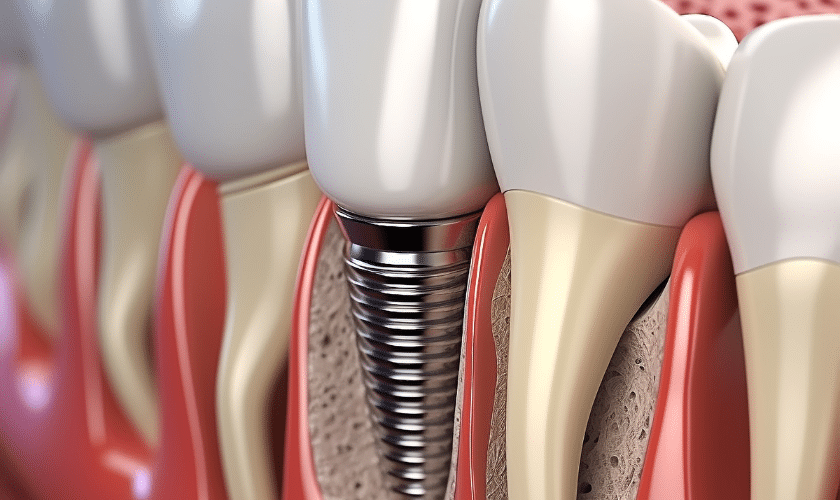

What are Dental Implants?

Dental implants are titanium posts that are surgically positioned into the jawbone beneath your gums. These posts serve as synthetic roots, offering a stable base for replacement teeth that closely resemble natural teeth in appearance, texture, and function. Unlike dentures, which can slip or cause discomfort, dentists can anchor dental implants firmly into the jawbone, making them a permanent and reliable solution.The American Dental Association recognizes dental implants as a significant advancement in dentistry due to their ability to restore both function and aesthetics effectively.

- Endosteal Implants: These are the most prevalent form of dental implants, typically inserted directly into the jawbone. Following the healing of the surrounding gum tissue, you’ll require a subsequent procedure to attach a post to the original implant. Finally, dentist will attach an artificial tooth (or teeth) to the post-individually, or grouped on a denture or bridge.

- Implant Placement: During a minor surgical procedure, the implant posts are placed into your jawbone. Over the next few months, the implants will bond with the bone in a process called osseointegration.

- Abutment Placement: Once your dentist integrates implants with your jawbone, he’ll attach the abutments (connector posts) to the implants to securely hold the artificial teeth in place.

- Placement of Artificial Teeth: Finally, custom-made artificial teeth (crowns, bridges, or dentures) are attached to the abutments, completing your smile restoration.